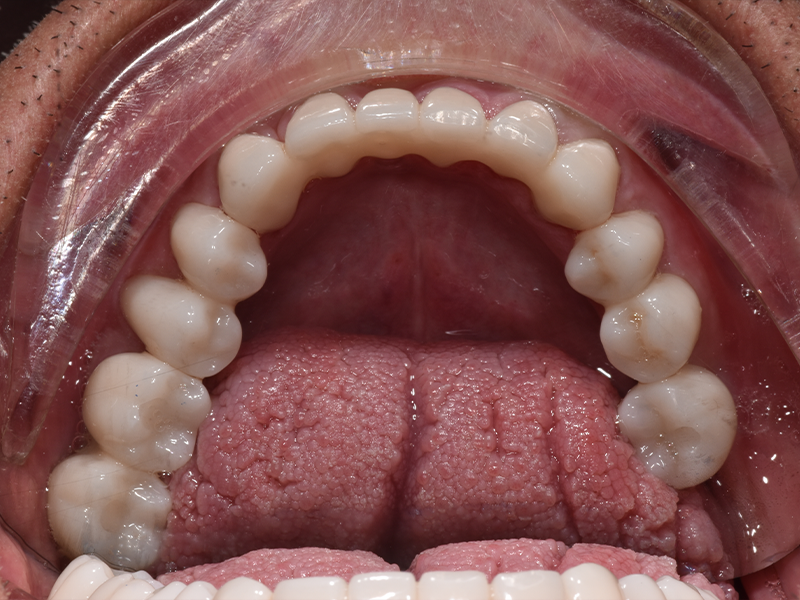

- Ricostruzione e allungamento di tutti i denti consumati

- Inserimento di impianti dentali per sostituire i molari mancanti

- Ripristino dell’armonia del sorriso e della corretta funzione masticatoria

Un lavoro graduale, durato circa 8 mesi, che ha trasformato il sorriso di Salvatore in maniera radicale.

Dopo